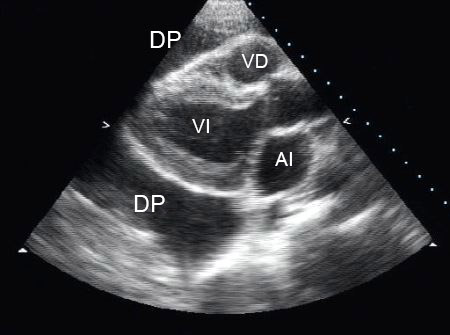

Vista paraesternal de eje largo de un derrame pericárdico (DP); AI = aurícula izquierda, VI = ventrículo izquierdo, VD = ventrículo derecho

De la colección del Dr. Rajdeep Khattar